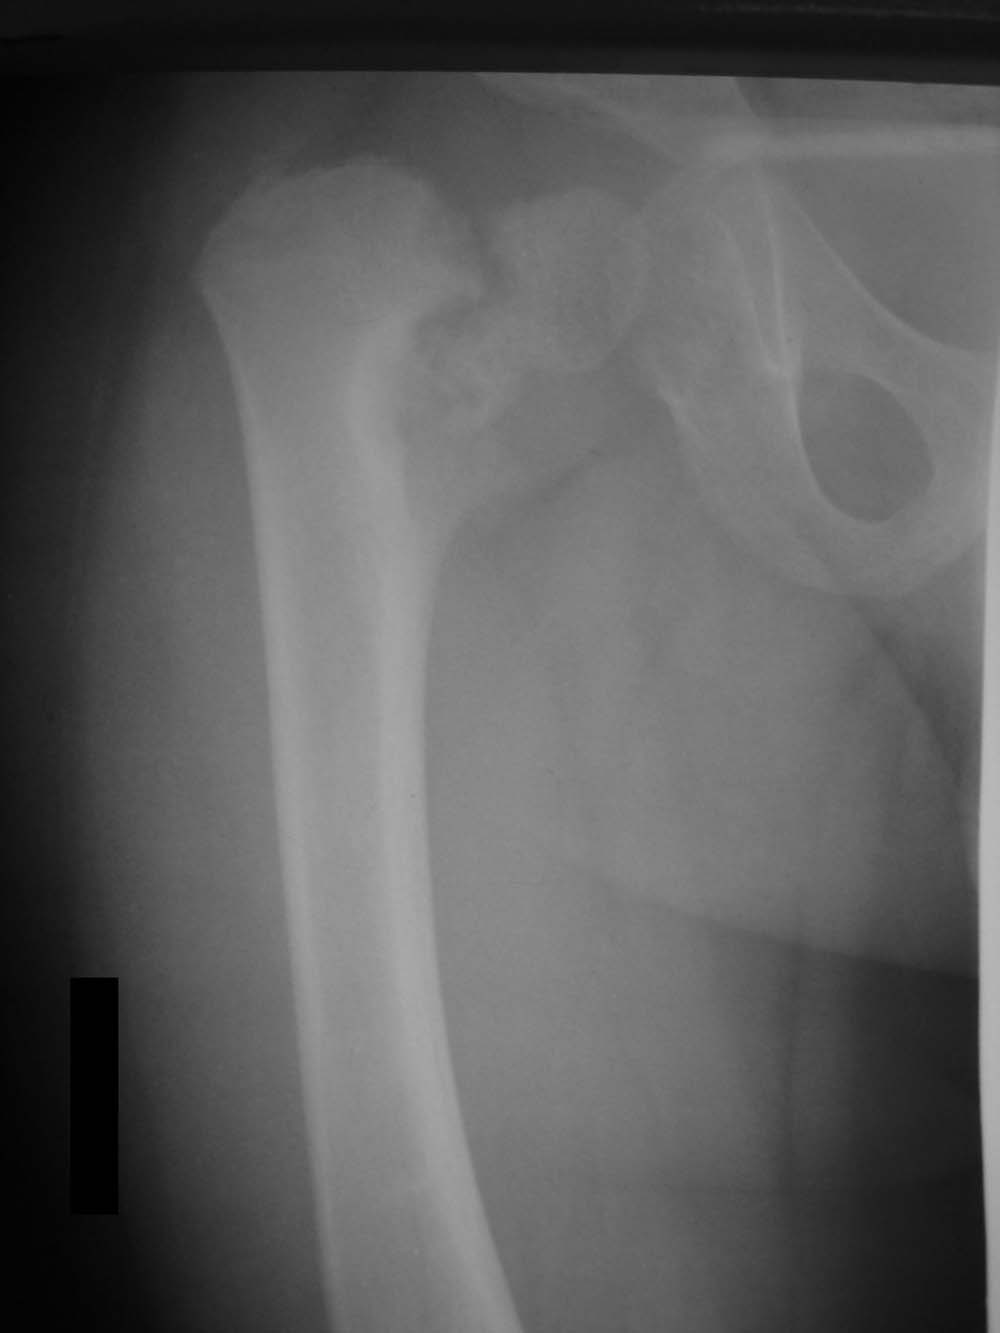

В представленном случае, по всей видимости, имеет место застарелый перелом со смещением отломков, в результате чего и произошло уменьшение шеечно-диафизарного угла.

Нет, травмы в данном случае не было. Имеет место дистрофическая coxa vara, вероятнее всего, врождённаяю. Эпифизеолиз головки, который мы видим на снимке, как мы считаем, наступил вследствие нарушений биомеханики в суставе - ШДУ практически 90 градусов. Добавлю, что факт травмы родители категорически отрицают. Ребёнок постепенно начал хромать, хромата усиливалась на протяжении 6 месяцев.